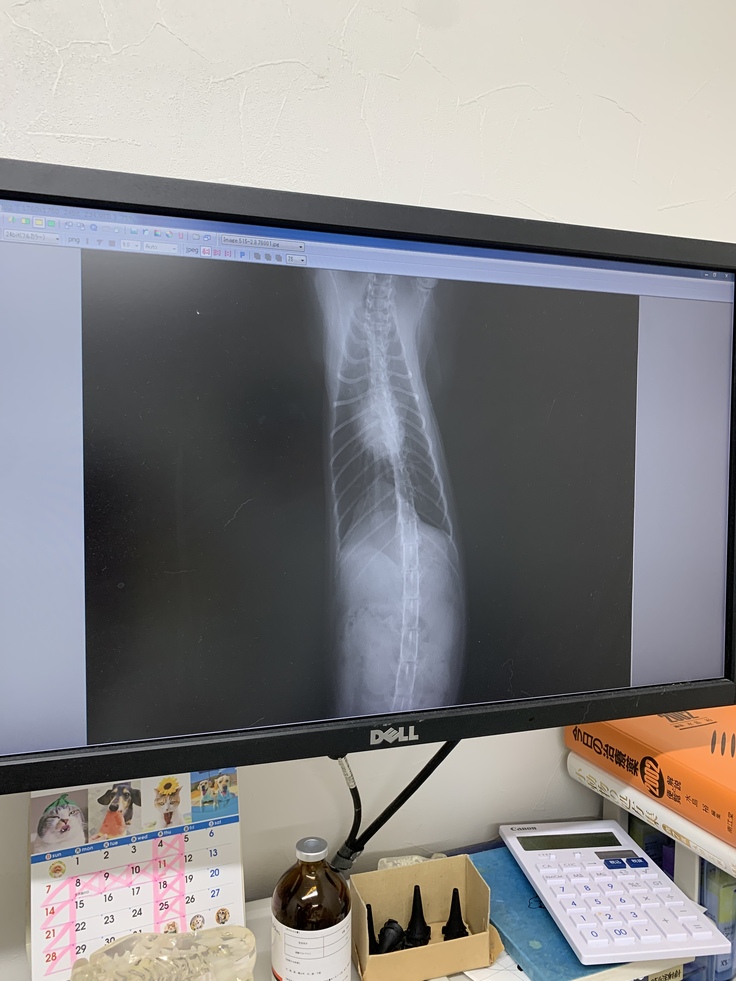

レントゲンは明らかに改善!

病気様に記載許可を頂いています。

ビアンカにはこのオンコビンがよく効くようで、これ以降は2週間に1回のオンコビン点滴と、毎日のステロイド経口投与、3−4日毎の抗がん剤(シクロフォスファミド)で過ごしています。